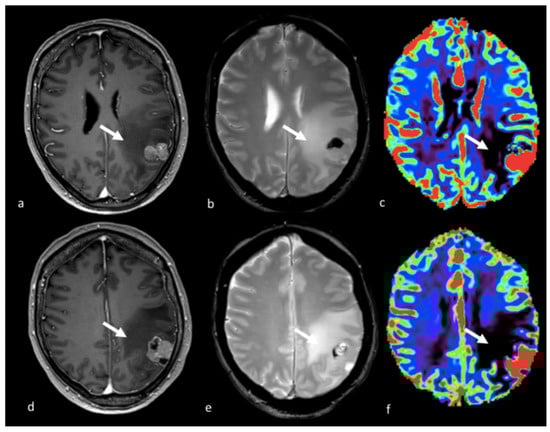

- Lee, E.J.; Ahn, K.J.; Lee, E.K.; Lee, Y.S.; Kim, D.B. Potential role of advanced MRI techniques for the peritumoural region in differentiating glioblastoma multiforme and solitary metastatic lesions. Clin. Radiol. 2013, 68, e689–e697. [Google Scholar] [CrossRef]

- Sternberg, E.J.; Lipton, M.L.; Burns, J. Utility of diffusion tensor imaging in evaluation of the peritumoral region in patients with primary and metastatic brain tumors. AJNR Am. J. Neuroradiol. 2014, 35, 439–444. [Google Scholar] [CrossRef]

- Neska-Matuszewska, M.; Bladowska, J.; Sasiadek, M.; Zimny, A. Differentiation of glioblastoma multiforme, metastases and primary central nervous system lymphomas using multiparametric perfusion and diffusion MR imaging of a tumor core and a peritumoral zone-Searching for a practical approach. PLoS ONE 2018, 13, e0191341. [Google Scholar] [CrossRef]

- Blasel, S.; Jurcoane, A.; Franz, K.; Morawe, G.; Pellikan, S.; Hattingen, E. Elevated peritumoural rCBV values as a mean to differentiate metastases from high-grade gliomas. Acta Neurochir. 2010, 152, 1893–1899. [Google Scholar] [CrossRef] [PubMed]